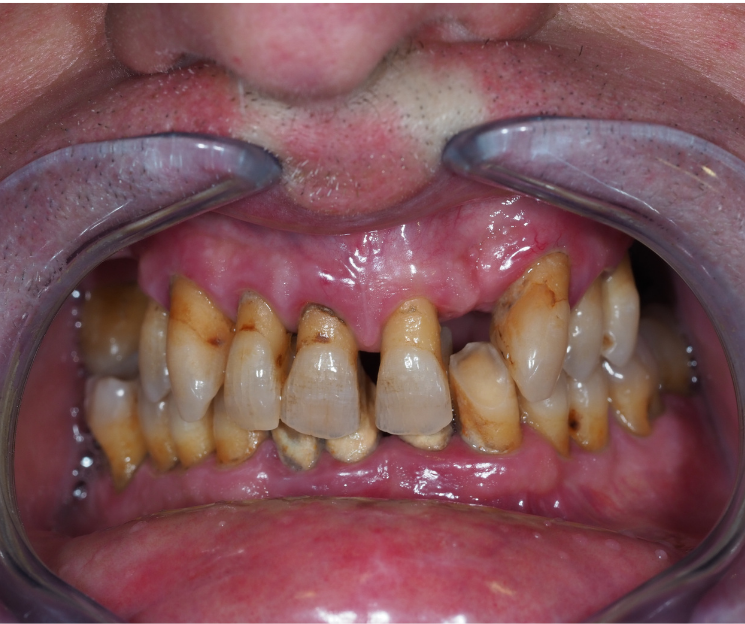

Clínica Dental especializada en la CDMX, Tijuana, Toluca, Cuernavaca, San Luis Potosí.  Colocamos  implantes dentales monofásicos de carga inmediata, también conocidos como implantes de una sola pieza. Somos una alternativa más rápida, estética y menos invasiva frente a los implantes tradicionales.

*Procedimiento: Colocación de implantes dentales monofásicos. A diferencia de los tradicionales (bifásicos), estos son de una sola pieza (tornillo y pilar integrados), lo que permite, colocar el implante y la prótesis provisional en una sola intervención o en un plazo de 3 días.

El tratamiento con implantes dentales está especialmente indicado para personas que han perdido una o más piezas dentales y desean recuperar su sonrisa a través de una solución fija, estable y definitiva, sin necesidad de prótesis removibles. Incluso aquellos pacientes que presentan poco hueso pueden ser candidatos, gracias a técnicas avanzadas que permiten trabajar con alternativas como la implantología monofásica. Además, es una excelente opción para quienes desean reemplazar prótesis removibles incómodas o poco estéticas, mejorando significativamente su calidad de vida, comodidad y confianza al sonreír.